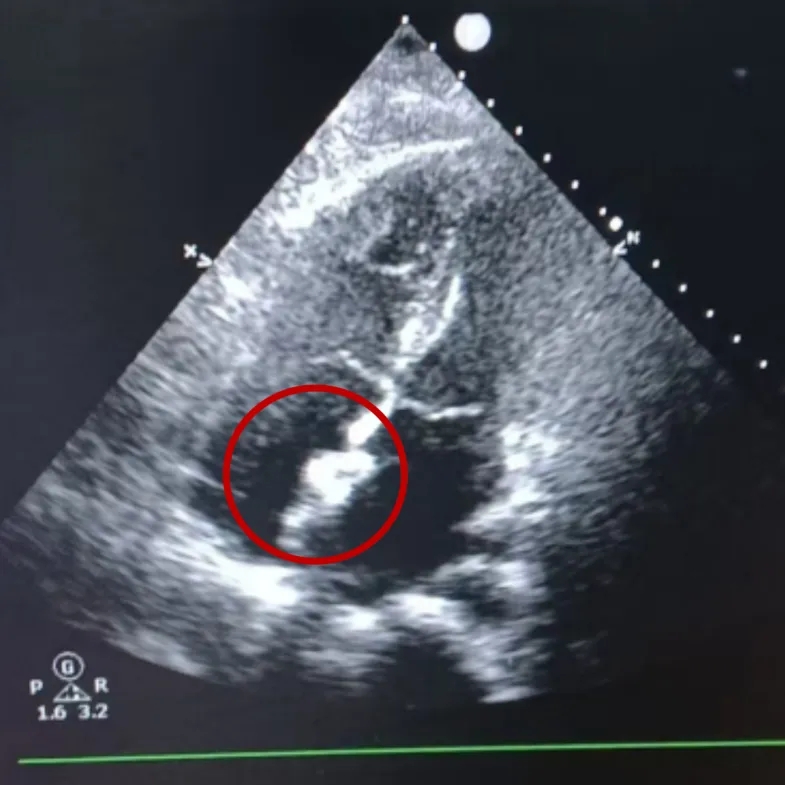

四腔心切面

双房心切面

超声下可见封堵器稳定夹持在房间隔两侧,盘面贴合,形态良好

出院前超声复查

超声所见:房间隔中部可见封堵器强回声,封堵后房间隔中部可见封堵器强回声,位置固定,CDFI:目前房水平未见明显过隔血流信号。右室轻大,CDFI:收缩期,二尖瓣房侧可见少量反流信号;收缩期,三尖瓣房侧可见少量反流信号。

-

超声提示:房间隔缺损封堵术后房水平未见残余分流、右室轻大、二尖瓣少量反流、三尖瓣少量反流。